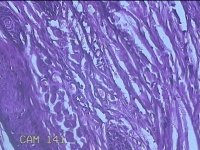

左眼外侧缘上肿物

性别

女

年龄

60岁

临床诊断

痣;疣

左眼上睑缘白色丘疹1年余。

灰白粉红色肿物0.8x0.3x0.2cm两个,表面光滑。